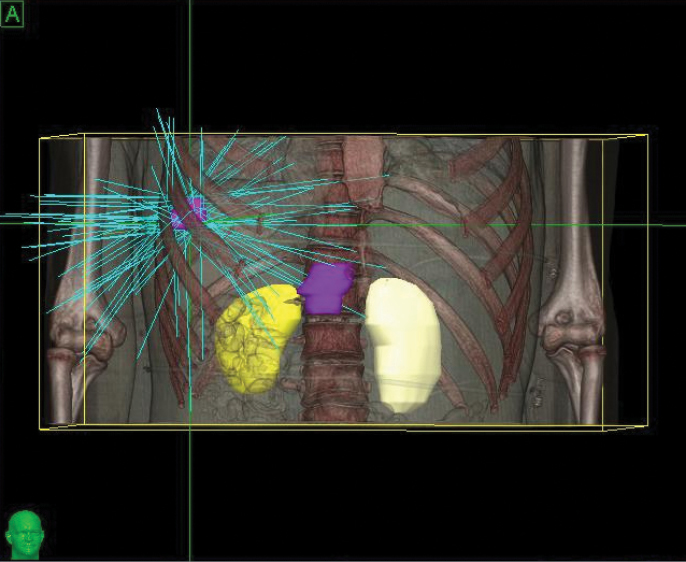

Phase 1 treatment covered the right lower lobe and hilar nodes, divided into two targets. The prescription was 48 Gy, delivered in four 12 Gy fractions for each of the two targets. Bilirubin fluctuations were noted during the course of therapy, but gradually returned to normal after treatment. One month after radiotherapy, a CT scan showed tumor shrinkage. The left lobe had sufficiently enlarged in compensation, so the second stage of treatment was initiated.

Phase 2 treatment covered the right upper lobe, divided into two targets: The prescription was 39 Gy, delivered in three 13 Gy fractions for each of the two targets.

“The patient lived more than two years with good quality of life after initial diagnosis, when life expectancy would have been one month without CyberKnife treatment.”